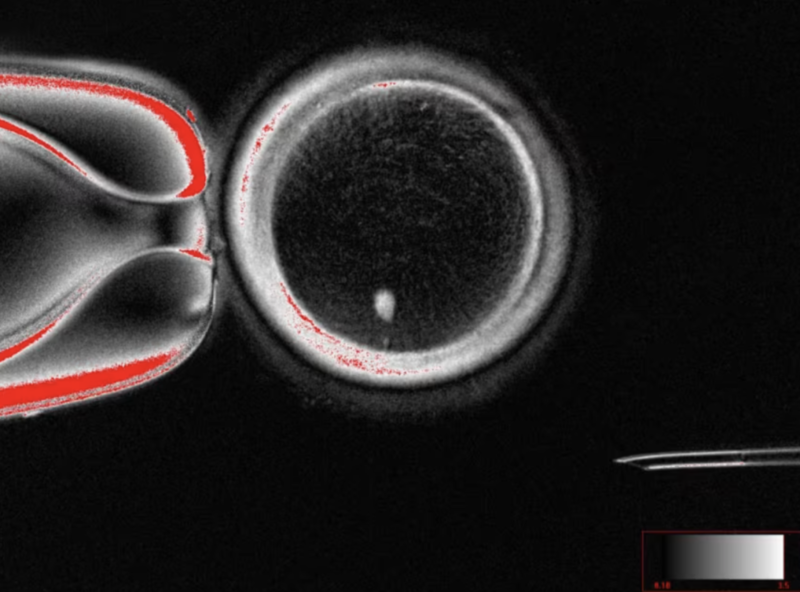

成功了吗?某种程度上是的。研究团队制造出了82枚功能性卵子,然后用来自男性的精子进行体外受精,结果真的形成了早期胚胎。

虽然没有一个胚胎被培育到植入阶段,但这个“能受精”的事实,本身就是一个“生殖大爆炸”。